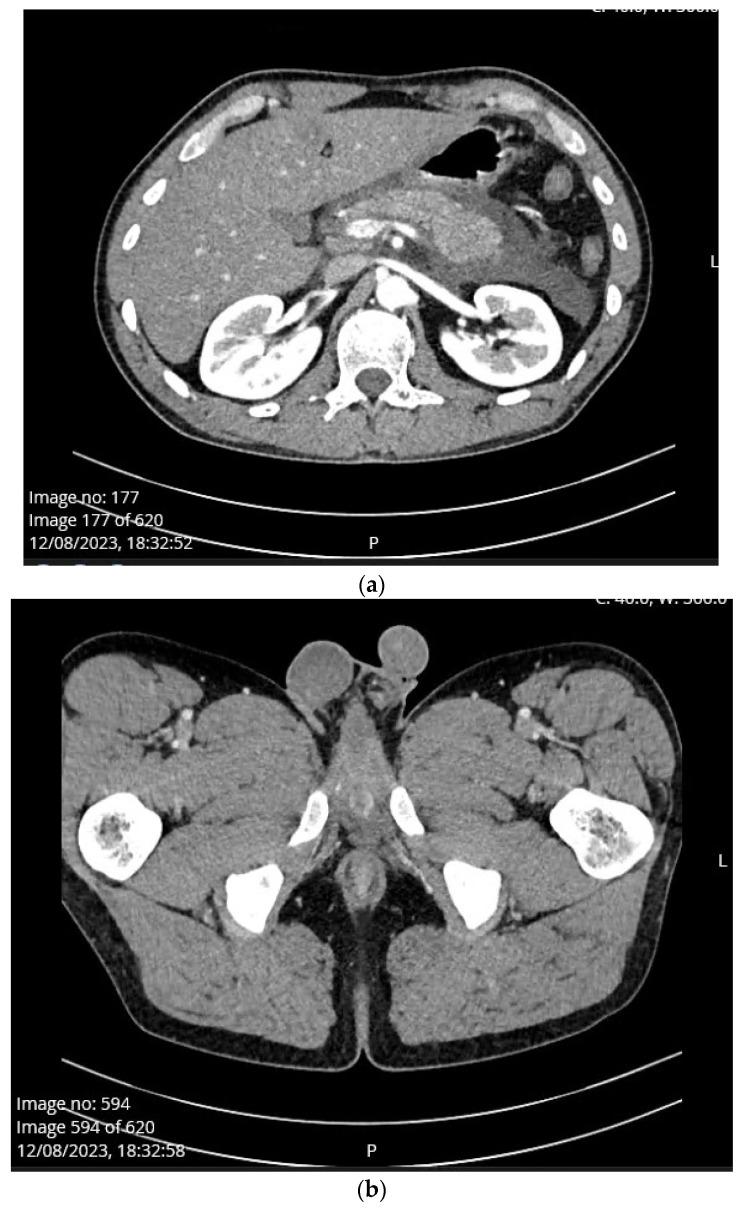

: Scrotal swelling or hydrocele is a rare complication of acute pancreatitis described in the literature. We present a case of penoscrotal swelling caused by the first attack of acute interstitial edematous alcohol-induced pancreatitis in a young male patient. : A 22-year-old man was admitted to the emergency unit due to diarrhea and vomiting since morning which was followed by severe abdominal pain. Urgent abdominal multislice CT scan showed steatosis, pancreatic swelling and acute peripancreatic fluid collection (interstitial edematous pancreatitis). Also, scan showed fluid between small bowel loops and along the anterior renal fascia, while there was minimal amount of fluid in the Douglas space. There was no sign of penoscrotal swelling. On the second day of admission, the patient developed left scrotal swelling and mild pain without erythema. On the fourth day, a control CT scan showed progression to moderately severe pancreatitis (CT severity index 4). Dilated scrotal veins of the pampiniform venous plexus with an increased caliber of the testicular veins were present on both sides, from the scrotum to the level of the inguinal canal. Penoscrotal swelling was significantly reduced on discharge. : Penoscrotal swelling is a rare complication or manifestation of acute inflammation of the pancreas. It is important to identify scrotal swelling caused by pancreatitis because in severe cases it can be related to possible infertility in the future.

一名 22 岁男性因腹泻和呕吐于当天上午入院,随后出现严重腹痛。紧急腹部多层 CT 扫描显示脂肪变性、胰腺肿胀和急性胰周液体积聚(间质性水肿性胰腺炎)。此外,扫描显示小肠环之间和前肾筋膜处有液体,而道格拉斯间隙内液体量较少。没有阴囊肿胀的迹象。入院第二天,患者出现左侧阴囊肿胀和轻度疼痛,但无红斑。入院第四天,对照 CT 扫描显示胰腺炎进展为中度重症(CT 严重指数 4)。双侧阴囊内精索蔓状静脉丛扩张,睾丸静脉增粗,从阴囊延伸至腹股沟管水平。出院时阴囊肿胀明显减轻。